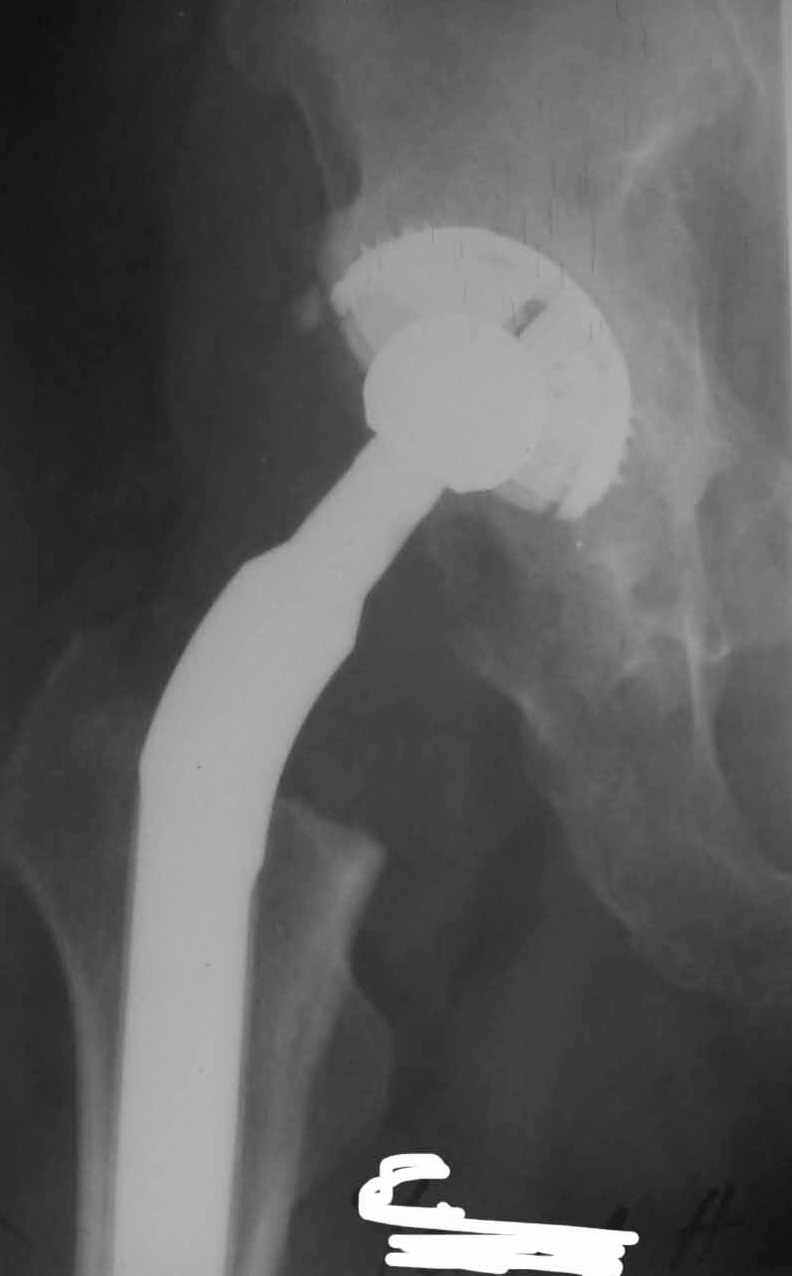

Дорогие коллеги.Мой хороший товарищ, сам травматолог-ортопед, прооперирован 1,5 мес назад. Естественно, начались проблемы. Хотелось бы узнать ваше мнениеи, главное,что делать дальше... Итак:Мужчина 50 лет.Д-з: Посттравматический деф.артроз правого тазобедренного сустава с выраженным болевым синдромом, стойкой комбинированной контрактурой иукорочением 3 см. Анамнез: 10 лет назад - сочетанная травма головы, груди, конечностей, таза... перелом заднего края вертлужной впадины и вывих бедра справа.Лечился консервативно. 25.05.94 - операция тотальное эндопротезирование правого тазобедренного сустава бесцементным эндопротезом (чашка Споторно 52, ножка Вагнера 225/21, головка L), дополнительная фиксация в кокситной гипсовой повязке в течение 3 нед. Спустя месяц после операции при поворачивании на бок в кровати произошел вывих головки эндопротеза. Под наркозом вывих вправили. Вот 10 дней лежит в постели. Что необходимо делать? Рентгенограммы до операции и после. Рентгенограммы в положении вивиха у меня отсутствуют. Ну наверное они и не столь важны, ведь вывих-то вправили. Учреждение и фамилию пациента, нашего коллеги, называть не буду. Он попросил меня собрать мнения - как ему жить дальше. Заранее благодарен. С уважением Александр Артемьев

1. Вертикальное положение чашки;

2. Нарушение угла антеверсии ножки (судя по изображению малого вертела

на послеопреационной рентгенограмме).

3. Комбинация этих двух причин.

4. Видимо, тенденция к вывиху была уже на столе - вот Вам и кокситная повязка с надеждой на фиксацию протеза рубцом.

Консультировать вывихи по рентгенограммам, не зная хода операции, дело не очень благодарное. Я думаю, что с датой операции Вы ошиблись и это был 2004 год? Тем не менее. Настораживают два фактора. Первое - не видно большого вертела. Если с мышцами обошлись грубо и их отсекли, то это очень грустно и нужна "связанная" пара, т.н. "constrain cup". Смущает хорошо прослеживаемый малый вертел и небольшая ретроверсия чашки. Возможно это (избыточная ретроверсия ножки и чашки) могло послужить причиной вывиха. Обычно гипсовая повязка после операции не накладывается, значит, были глубокие сомнения у оперировавшего хирурга. В этом случае - ревизия с перестановкой как минимум - ножки, а как максимум - обоих компонентов.

1. AP X ray of the Pelvis is a must. It will likely show that right hip/ femur is longer than left. Even based on Rt Hip AP X Ray it is my impression.

2. 2. Acetabular component is not vertical but rather anteverted, and also small ( small size was likely used because of the deficient posterior wall of the acetabulum).

3. Femoral component is malaligned relatively to the acetabular and combination of this factors (head is also small for this patient) is the reason for dislocation.( was likely anterior)